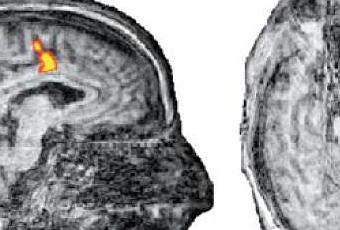

Les chercheurs britanniques et belges à l’origine de cette étude se sont penchés sur le cas de 54 patients plongés dans un état végétatif ou dans un état de conscience minimale après un accident ou une maladie. A l’évocation de deux activités distinctes – déambuler dans les pièces d’une maison ou jouer au tennis –, cinq des patients ont pu activer les régions du cerveau concernées. Cette interaction ne suffit pourtant pas à déterminer un état de conscience, ces réactions pouvant être de simples réflexes. Les chercheurs ont donc tenté d’obtenir des réponses à des questions simples et fermées. Comme l’explique très bien le site Nature News, “il est difficile, voire impossible, de déterminer quelles régions du cerveau sont activées quand une personne pense ‘oui’ ou ‘non’”. Aussi, les chercheurs ont demandé au patient de penser au tennis pour dire “oui” et à la maison pour dire “non”. Les zones du cerveau activées lors de ces deux activités sont distinctes et aisément identifiables grâce à l’IRM fonctionnelle.

L’un d’entre eux, un Belge dans le coma depuis cinq ans après un accident de la circulation, a réussi, grâce à cette technique, à répondre correctement. A la question “Est ce que votre père s’appelle Alexander ?”, le patient a répondu ‘”oui” en activant la zone du cerveau concernée. A la question ‘Est ce que votre père s’appelle Thomas ?’, le patient a répondu “non”. Ces deux réponses étant les bonnes. En tout, le patient a bien répondu à cinq des six questions qui lui ont été posées. Précisons que les scientifiques qui avaient la tâche d’étudier les IRM ne connaissaient pas les réponses aux questions pour éliminer les biais inhérents à l’analyse.

Photo : New England journal of medecine